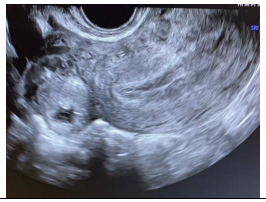

Paciente de 33 anos, comparece ao pronto atendimento com queixa de dor abdominal aguda de moderada intensidade. Nega comorbidades, nega uso de medicações, refere atraso menstrual de 20 dias. Na avaliação ecográfica apresenta a seguinte imagem:

A imagem ecográfica se correlaciona com diagnóstico de

Paciente de 33 anos, comparece ao pronto atendimento com queixa de dor abdominal aguda de moderada intensidade. Nega comorbidades, nega uso de medicações, refere atraso menstrual de 20 dias. Na avaliação ecográfica apresenta a seguinte imagem:

A imagem ecográfica se correlaciona com diagnóstico de